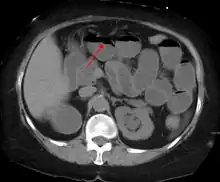

Contrast enema or small bowel series or CT scan can be used to define the level of obstruction, whether the obstruction is partial or complete, and to help define the cause of the obstruction. The appearance of water-soluble contrast in the cecum on an abdominal radiograph within 24 hours of it being given by mouth predicts resolution of an adhesive small bowel obstruction with sensitivity of 97% and specificity of 96%.[18]

Causes of bowel obstruction include adhesions, hernias, volvulus, endometriosis, inflammatory bowel disease, appendicitis, tumors, diverticulitis, ischemic bowel, tuberculosis and intussusception.[1][2] Small bowel obstructions are most often due to adhesions and hernias while large bowel obstructions are most often due to tumors and volvulus.[1][2] The diagnosis may be made on plain X-rays; however, CT scan is more accurate.[1] Ultrasound or MRI may help in the diagnosis of children or pregnant women.[1]